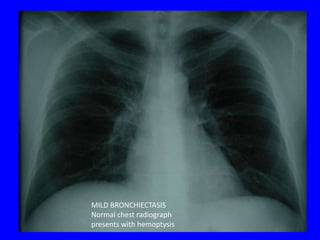

MILD BRONCHIECTASIS

Normal chest radiograph

presents with hemoptysis